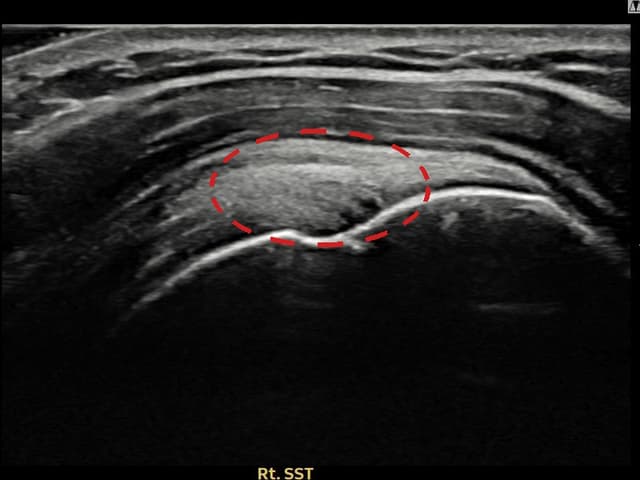

[촬영시기:23.09.01~23.11.03]

[어깨인대 축소봉합술] 우측 어깨 통증이 수개월간 지속되어 내원하셨습니다.